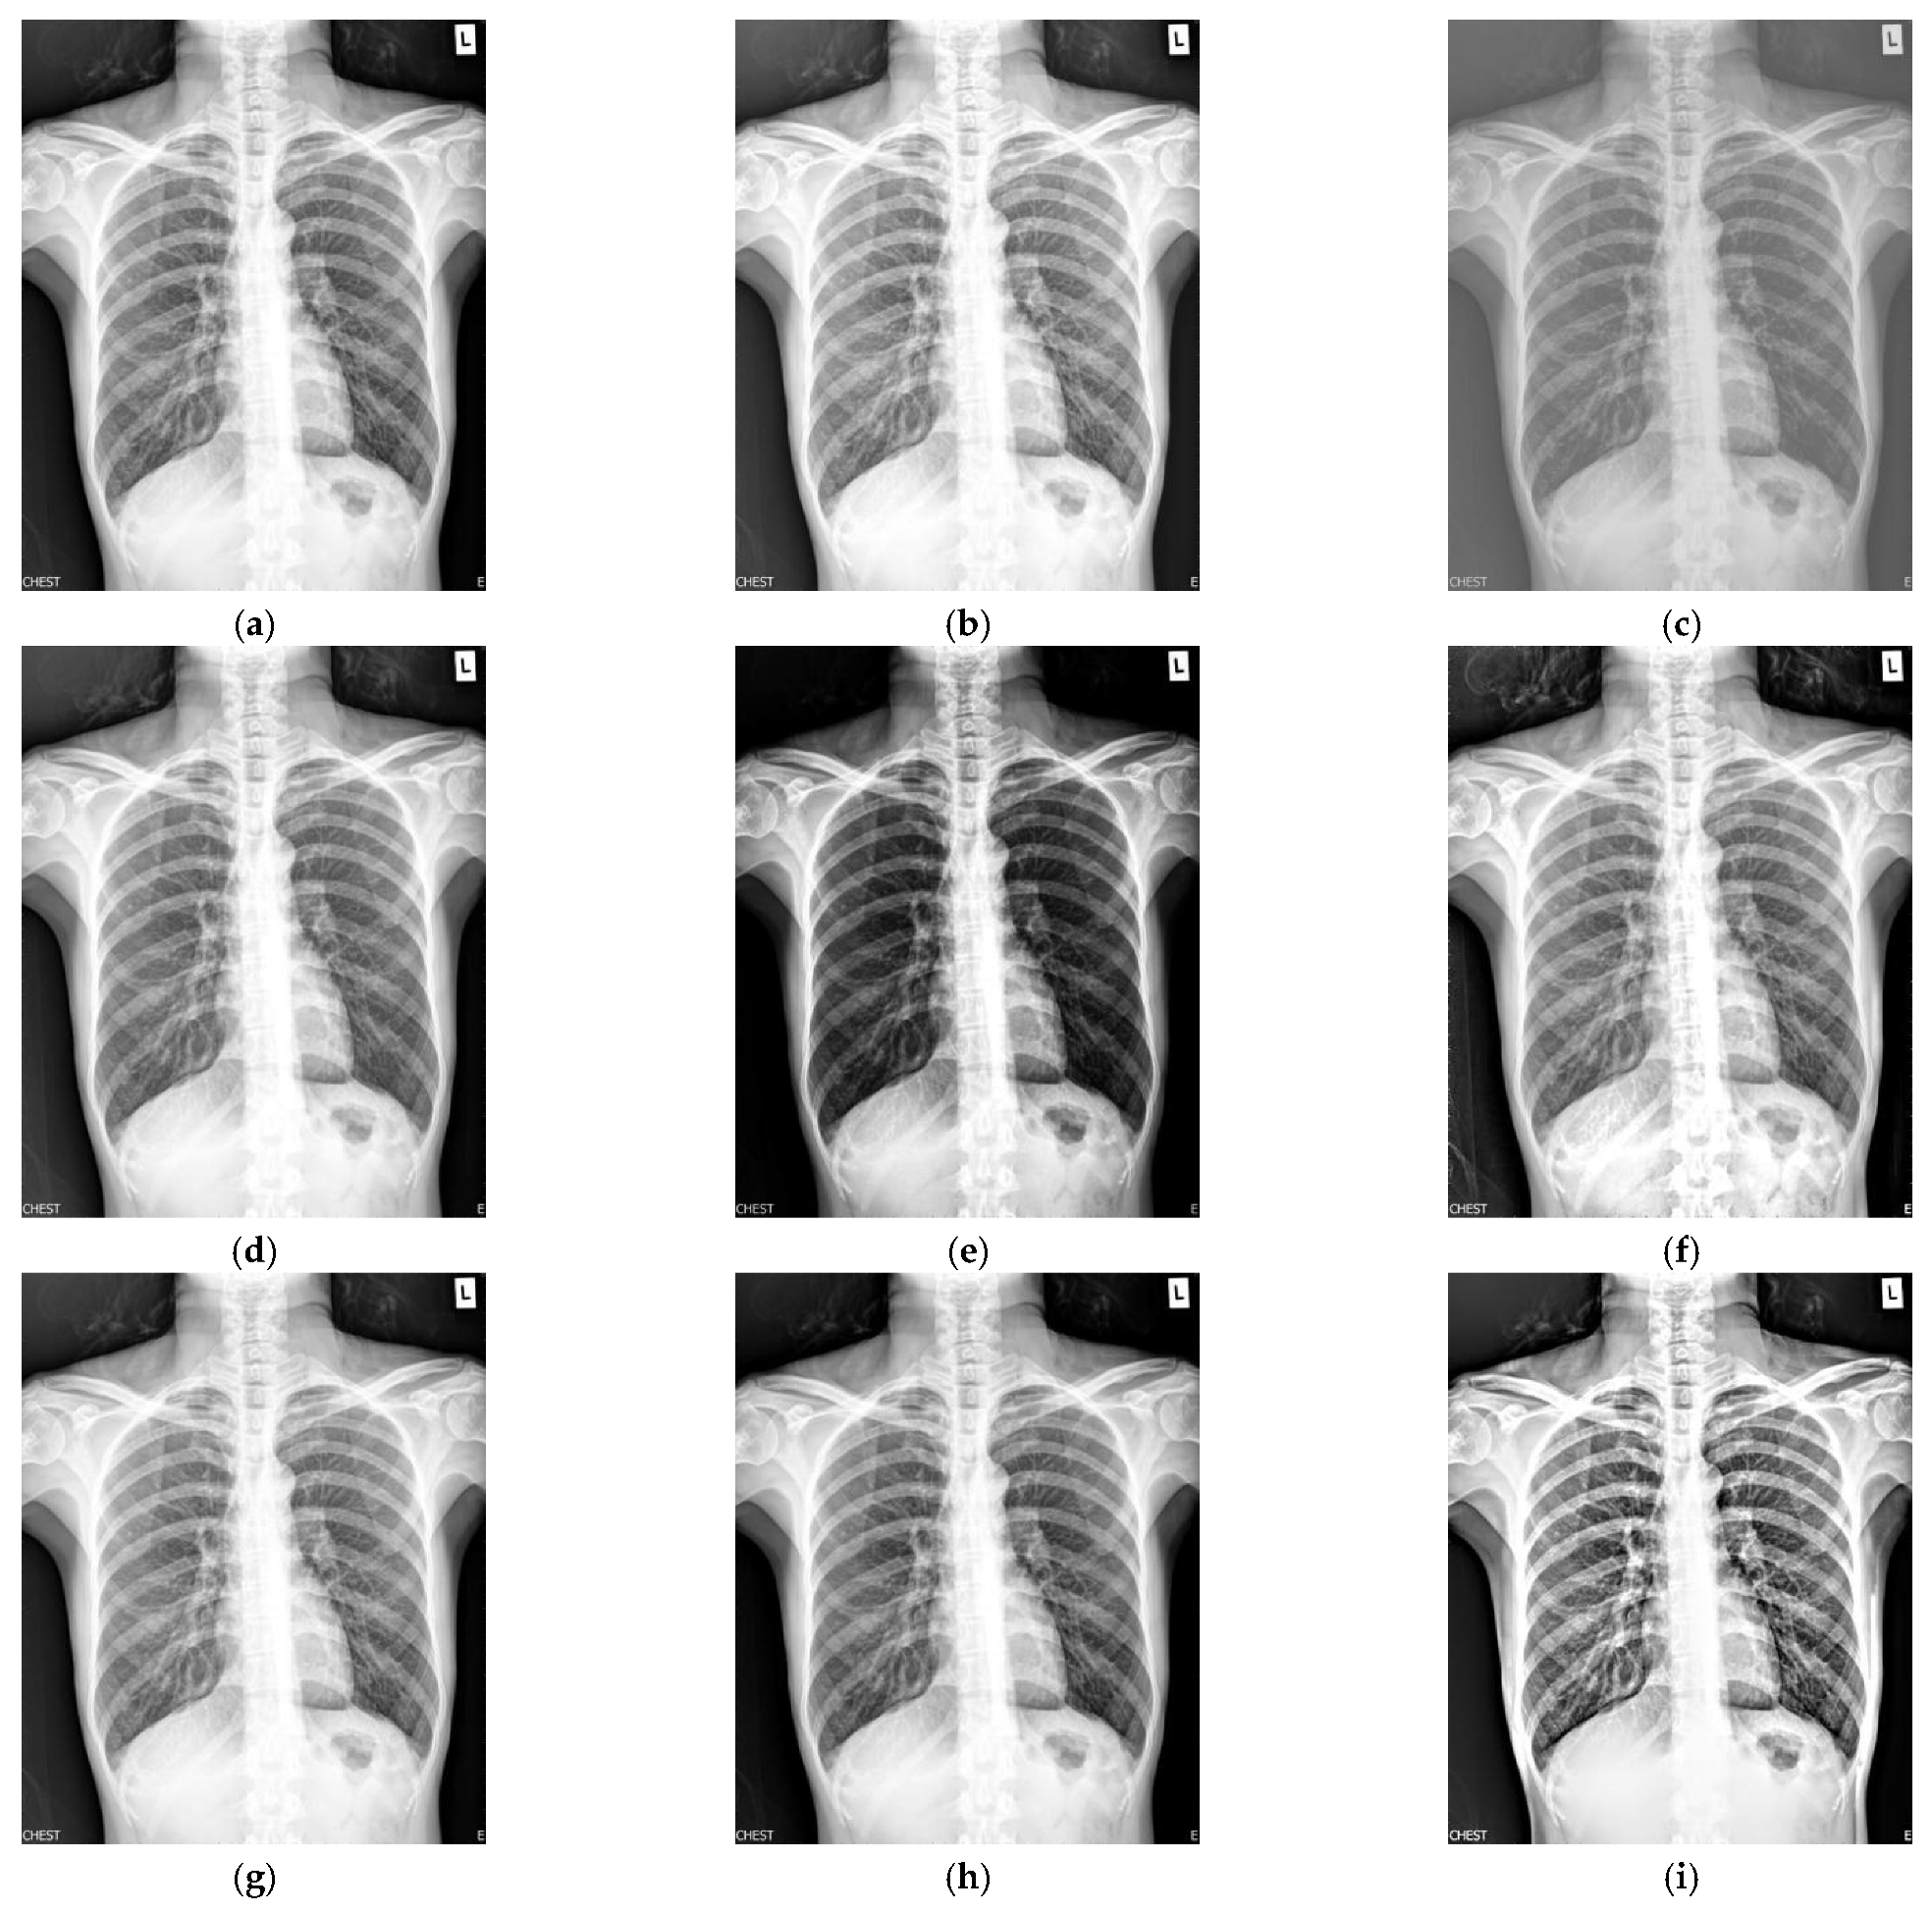

Figure 1 shows the enhancement images of eight methods experimented on X-ray image 1. Figure 1a shows the original X-ray image 1; Figure 1b shows the image obtained by McCann, and the image is too bright; Figure 1c shows the image achieved by RLBHE—the image is too dark and the performance of enhancement is poor, the details of the image are difficult to ascertain; Figure 1d is the result obtained by RESIHE—the definition of the image is low; Figure 1e shows the image enhanced by TBCSSR; Figure 1f represents the image obtained by GDGIF—the image has a lot of noise; Figure 1g and Figure 1h show the result enhanced by SMIPC and FuzzyII, respectively, and the images have poor enhancement performance; Figure 1i is the image achieved by the proposed method—it has moderate brightness and better clarity. Table 1 is the evaluation index values of various algorithms in Figure 1. From this table, we can denote that the values of AG, ALC, SF and MG obtained by the proposed technique are the best; the value of H achieved by SMIPC is the best, and the corresponding value obtained by the proposed method is still ranked second.

Figure 1.

Comparison on X-ray image 1. (a) Original image; (b) McCann; (c) RLBHE; (d) RESIHE; (e) TBCSSR; (f) GDGIF; (g) SMIPC; (h) FuzzyII; (i) Proposed method.

Table 1.

The metric data of eight methods on X-ray image 1.